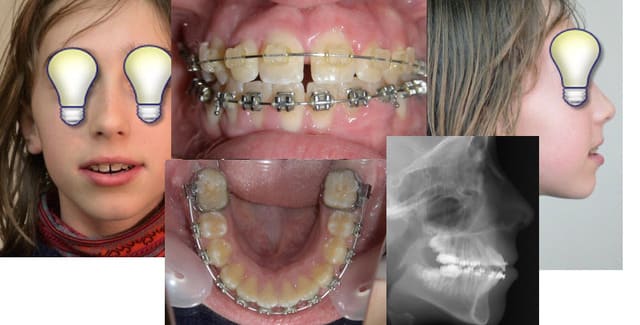

Tiens, Jeamba, ici la pauvre gamine ne peut même plus fermer les lèvres tellement ça déborde de partout. Ses parents ne la reconnaissaient plus. "reformage d'arcade" qu'ils disaient !

Le cas que tu montre, toi, N'A PAS été traité par un orthodontiste, c'est évident quand on voit les axes des dents, alors que celui-ci l'est par quelqu'un qui a tes idées.